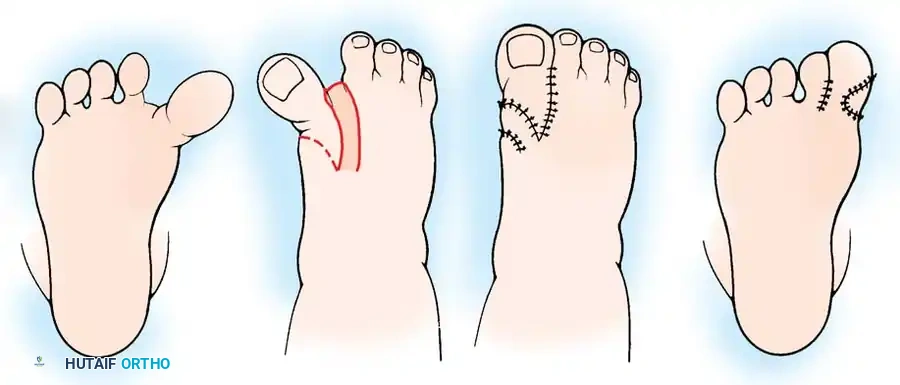

Metatarsus adductus is clinically stratified into mild, moderate, or severe categories based on the heel bisector method described by Bleck. This is assessed by viewing the plantar aspect of the weight-bearing foot and drawing a longitudinal line bisecting the heel.

Fig. 1: The heel bisector defines the relationship of the heel to the forefoot. From left to right: normal (bisecting second and third toes), mild metatarsus adductus (bisecting third toe), moderate metatarsus adductus (bisecting third and fourth toes), and severe metatarsus adductus (bisecting fourth and fifth toes).

- Mild Metatarsus Adductus: The heel bisector line passes through the third toe. Clinically, the forefoot can be passively abducted to the midline of the foot and beyond.

- Moderate Metatarsus Adductus: The heel bisector line passes between the third and fourth toes. The forefoot possesses enough flexibility to allow passive abduction to the midline, but usually not beyond.

- Severe (Rigid) Metatarsus Adductus: The heel bisector line passes through the fourth or fifth toe. The forefoot is rigid and cannot be passively abducted to the midline.

Fig. 5: The Farmer procedure for congenital hallux varus, utilizing a rotational skin flap to deepen the first web space and correct the medial tethering.

Fig. 6: Alternative Farmer procedure for congenital hallux varus, demonstrating the incision, capsular release, flap transposition, and application of a full-thickness skin graft.